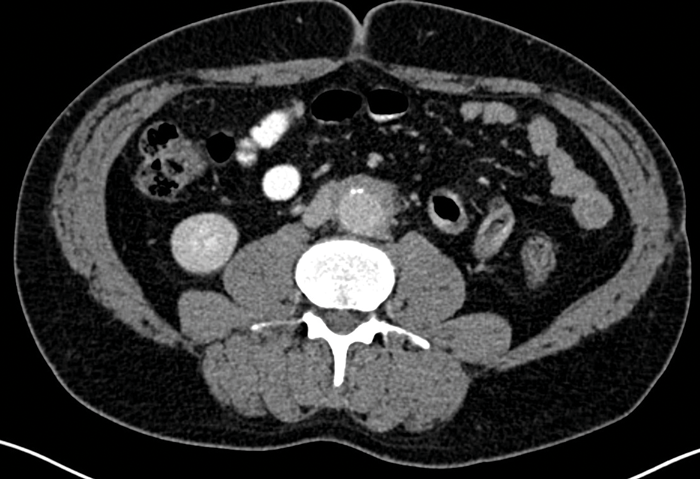

CT also allows detection of other causes of RPF, including malignancy, and is useful for follow-up purposes to assess if the fibrotic tissue is responding to treatment (Figure 4).

Figure 4: Portal venous phase CT abdomen in the same patient as Figures 2 and 3 showing that the

fibrotic tissue has markedly decreased in size compared with previous imaging, as a result of successful treatment.